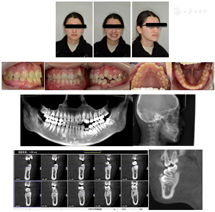

患者面部左右不对称,颏部略向左偏斜;直面型,鼻唇角正常。恒牙列,骨性Ⅰ类,安氏Ⅲ类。上颌牙列Ⅰ°拥挤,23牙颊侧倾斜。下颌牙列Ⅰ°拥挤,34牙口内未见,74牙滞留,下沉。33牙冠向远中倾斜,35,36牙冠向近中倾斜。左侧尖牙远中关系,双侧磨牙开始近中关系;前牙覆盖基本正常,下颌中线向左偏斜约1.5 mm。影像学检查:CBCT示74牙滞留,下沉;34牙横位埋伏阻生于74牙根的远中,34牙根周围牙周膜影像清晰,与周围骨质无粘连(图1)。

矫治设计拔除18,28,38。使用Tip-Edge Plus金属矫治器,排齐上下颌牙列,下颌更换钢丝至不锈钢圆丝时,口腔外科拔除滞留乳牙74,同期34牙开窗,黏结牵引装置,慢慢牵引34牙至正常位置。

矫治过程:初戴时上下颌全口牙列黏结Tip-Edge Plus托槽及磨牙颊面管,上下颌牙列放置0.014镍钛丝。上颌弓丝更换的顺序为:0.016镍钛丝,0.018镍钛丝,0.016×0.022镍钛丝,0.018×0.025镍钛丝,0.018×0.025不锈钢方丝。下颌弓丝更换顺序为:0.016镍钛丝,0.018镍钛丝,0.020不锈钢圆丝,0.016×0.022镍钛丝,0.018×0.025镍钛丝,0.018×0.025不锈钢方丝。下颌弓丝更换至0.020不锈钢圆丝时,口腔外科拔除74牙,34牙开窗,黏结牵引装置。牵引装置与下颌弓丝之间弹性牵引。同时为防止埋伏牙两侧的牙齿因受牵引力向中间倾斜,在33牙位的托槽上安装牙根向远中倾斜的正轴簧,35牙位的托槽上安装牙根向近中倾斜的正轴簧。待34牙冠完全萌出后,34牙去除牵引装置,黏结托槽,在主弓丝为0.020不锈钢圆丝不变的前提下,于下颌托槽的辅弓管内放置0.012 NiTi丝辅助排齐,待34牙冠牵引到正常高度后,34牙位的托槽安装牙根向近中的正轴簧用来竖直牙根。最后阶段精细调整,对齐上下颌中线,关闭剩余间隙(图2)。

本病例采用CBCT三维图像,对阻生牙的位置提供矢状面、冠状面及轴面等多平面的重建图像,且精度高,不存在失真的随意放大及旋转。通过CBCT对阻生前磨牙准确定位,确定外科手术开窗的部位和正畸牵引力的方向。本病例中,34的萌出间隙是足够的,不用额外扩展间隙。矫治前CBCT显示34牙根发育正常,仅根尖处1 mm左右的牙根弯曲,34牙周膜影像清晰,与周围骨质无粘连,与35牙根无粘连。采用Tip-Edge Plus技术,利用硬度较高的不锈钢丝作为承受牵引力的钢丝,同时托槽的竖管安装正轴簧,控制牙轴,以免加重缺牙间隙两侧的牙齿向缺隙侧倾斜,为埋伏牙的牵引提供了足够的支抗需求。该牙的牵引过程主要包括两个阶段,第一阶段是通过垂直向的牵引力,先把埋伏牙牵引出牙龈外,待牙冠高度接近合平面,同时牙冠颊侧面暴露充分以后,进入第二阶段,即在牙齿的颊侧黏结托槽,利用该托槽自带的竖管安装正轴簧,辅助竖直牙轴。另外该患者配合度极高,能坚持按约复诊,且有良好的口腔卫生习惯,这也是埋伏牙牵引成功的条件之一。最终经过系统矫正,成功牵引出埋伏阻生牙,排齐上下牙列,建立良好的咬合关系。